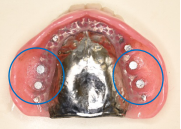

【義歯を外したところ】

【マグネット式総入れ歯】

青丸は組み込まれたマグネット